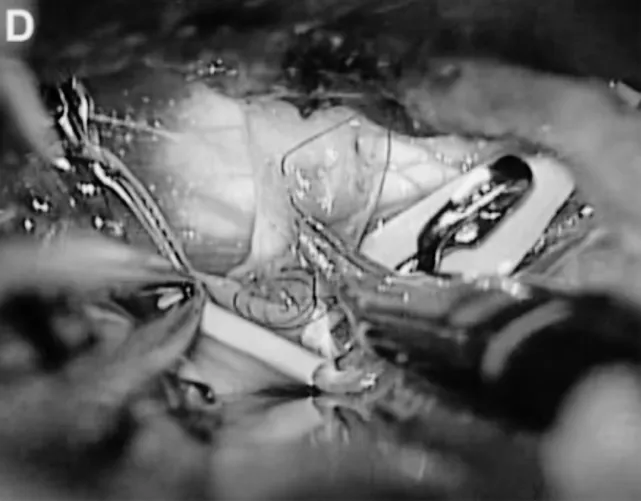

医疗团队经左侧颞下入路,选择后颞动脉作为受体动脉(图C、D),成功完成搭桥和孤立术。手术过程精度要求极高,需避免周围神经血管损伤,确保吻合口无渗漏。

C、D. 选择颞后动脉(箭头标注)作为受体动脉,经左侧颞下入路采用连续缝合行颞浅动脉-颞后动脉吻合。